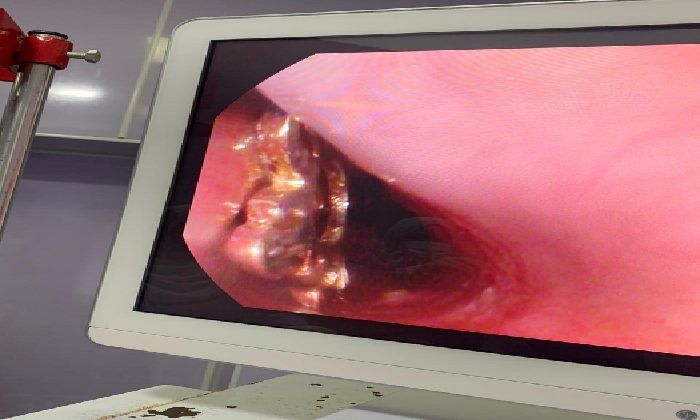

منظار جراحي

وأوضح وكيل وزارة الصحة أن قسم المناظير بمستشفى أبو كبير شهد نجاح مميز في إنقاذ الطفلة التي تبلغ من العمر ٥ سنوات، وقامت بابتلاع سلسلة معدنية حادة ومدببة وأطرافها قادرة على إحداث جروح أو ثقوب بالزور أو داخل المعدة، وبعد استقبالها مساء أمس الثلاثاء بمستشفى مشتول السوق المركزي، وتم التنسيق السريع من خلال مركز الخدمات الطارئة ١٣٧ بالمديرية، وتحويل الحالة بسيارة الإسعاف إلى مستشفى أبو كبير في وقت قياسي، وتم التدخل العاجل بالمنظار بعد إجراء كافة الفحوصات الطبية اللازمة لها، واستخراج السلسلة من المعدة دون أي مضاعفات، وسط متابعة وتدخل فوري من الفريق الطبي بقيادة الدكتور محمد عصام خلال الفترة المسائية.